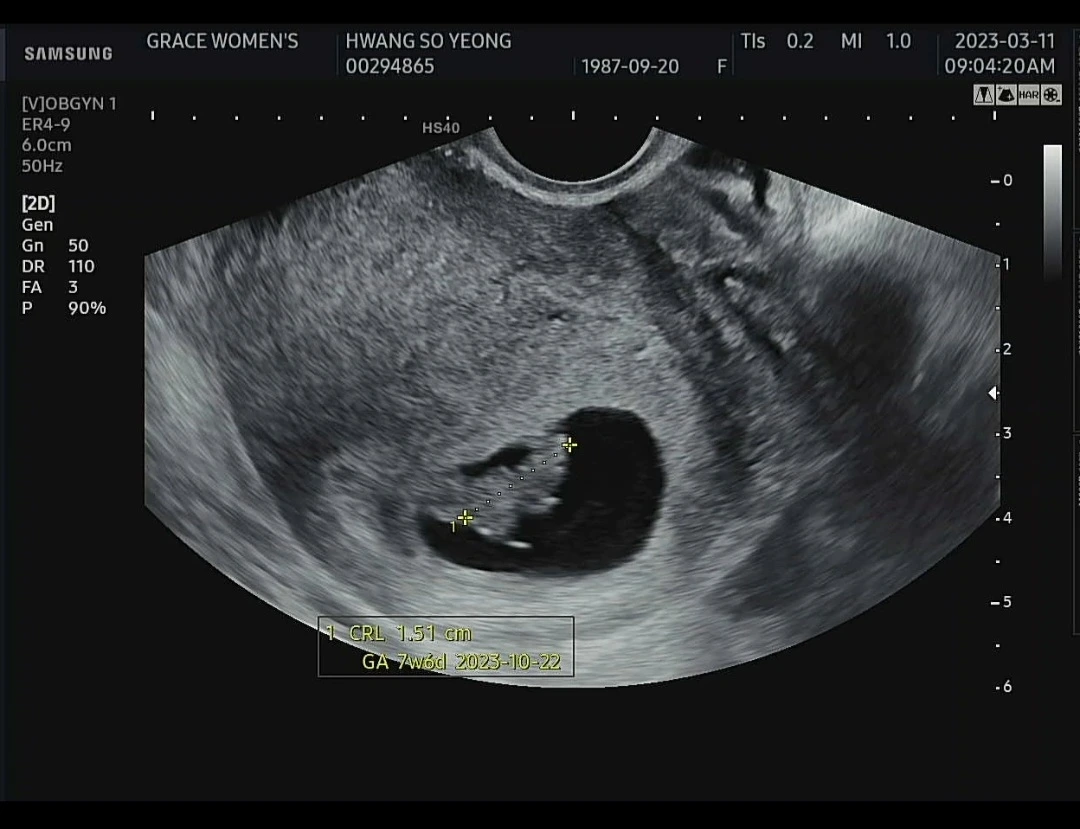

기쁨과 불안감이 공존했다. 두 차례의 유산(계류유산, 화학유산) 경험이 있었기에 이 아이를 이번에도 못 지키면 어쩌지 공포감이 있었다. 소랑이는 4주 1일 점 같은 아기집을 지었고 5주 6일엔 2mm의 크기를 자랑하며 난황에 매달린 모습으로 엄마, 아빠에게 인사했다. 7주 6일엔 170 BPM이 넘는 쿵쾅쿵쾅 심장소리와 깜찍한 1.5cm 이 등신 몸매로 반하게 했다.

손과 발이 생긴 귀여운 9주 6일 이 등신 소랑이를 만나러 갈 생각에 설렘 가득이었는데 소랑이의 심장은 뛰지 않았다. 8주 4일께쯤 크기로 성장이 멈춰있었고 쿵쾅거리던 심장도 조용했다. 반짝거리던 심장이 내 눈에도 보이지 않았다. 의사 선생님은 유산의 명확한 이유가 없다는 얘기와 함께.. 수술 날짜를 잡자고 했다. 수술 후 태아의 유전자 검사를 해보자고 했다.